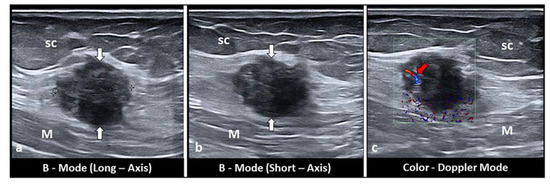

- Bozkurt, M.; Çil, A.S.; Bozkurt, D.K. Intramuscular abdominal wall endometriosis treated by ultrasound-guided ethanol injection. Clin. Med. Res. 2014, 12, 160–165. [Google Scholar] [CrossRef]